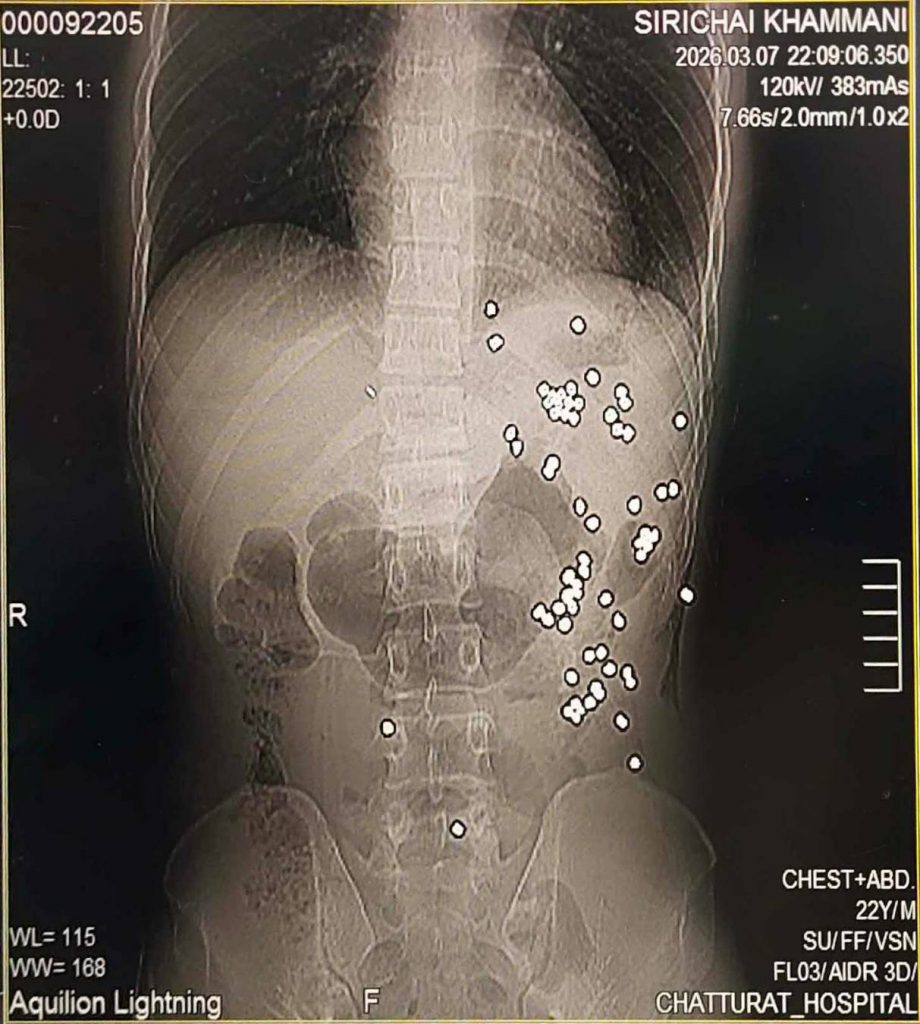

จากการตรวจสอบพบว่า ผู้บาดเจ็บคือ นายศิริชัย หรือ “คิง” อายุ 23 ปี ชาวบ้านโนนคร้อ ต.บ้านขาม อ.จัตุรัส จ.ชัยภูมิ ซึ่งมีอาชีพเป็น พนักงานรังวัดที่ดิน และยังเป็น นักฟุตบอลเดินสาย ถูกยิงเข้าบริเวณใต้ลิ้นปี่และถูกมีดฟันที่แขนซ้าย โดยแพทย์พบว่ามี ลูกกระสุนฝังอยู่ในร่างกายมากถึง 67 เม็ด อาการยังอยู่ในขั้นสาหัส ต้องส่งต่อรักษาที่ โรงพยาบาลชัยภูมิ